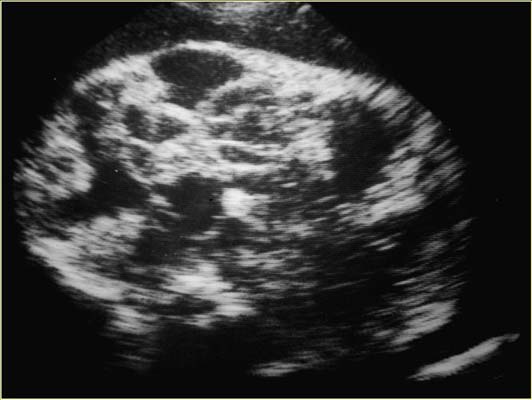

Hémolymphangiome cervical 35w